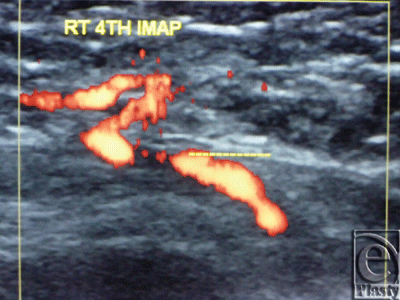

The site of the detectable perforator(s) was projected by a colored marker on the patient's skin so as to estimate the label remoteness (representing the perforation site) from the sternum (Fig 2), and the number of encountered perforators parasternally in each investigated space was counted as well. The inner diameter of each perforator was measured (Fig 3). Figures 4 to 8 show color duplex photos for perforators penetrating the fascia to reach the dermoglandular target.

| Figure 3. Color Duplex photo shows the diameter and depth of a certain visualized 5th internal mammary artery perforator from the skin surface. The point of measurement was at the perforation point. |

![]() |

| Figure 4. Color Duplex photo shows a 4th internal mammary artery perforator while perforating the superior surface of the pectoralis major muscle (the dashed line). |